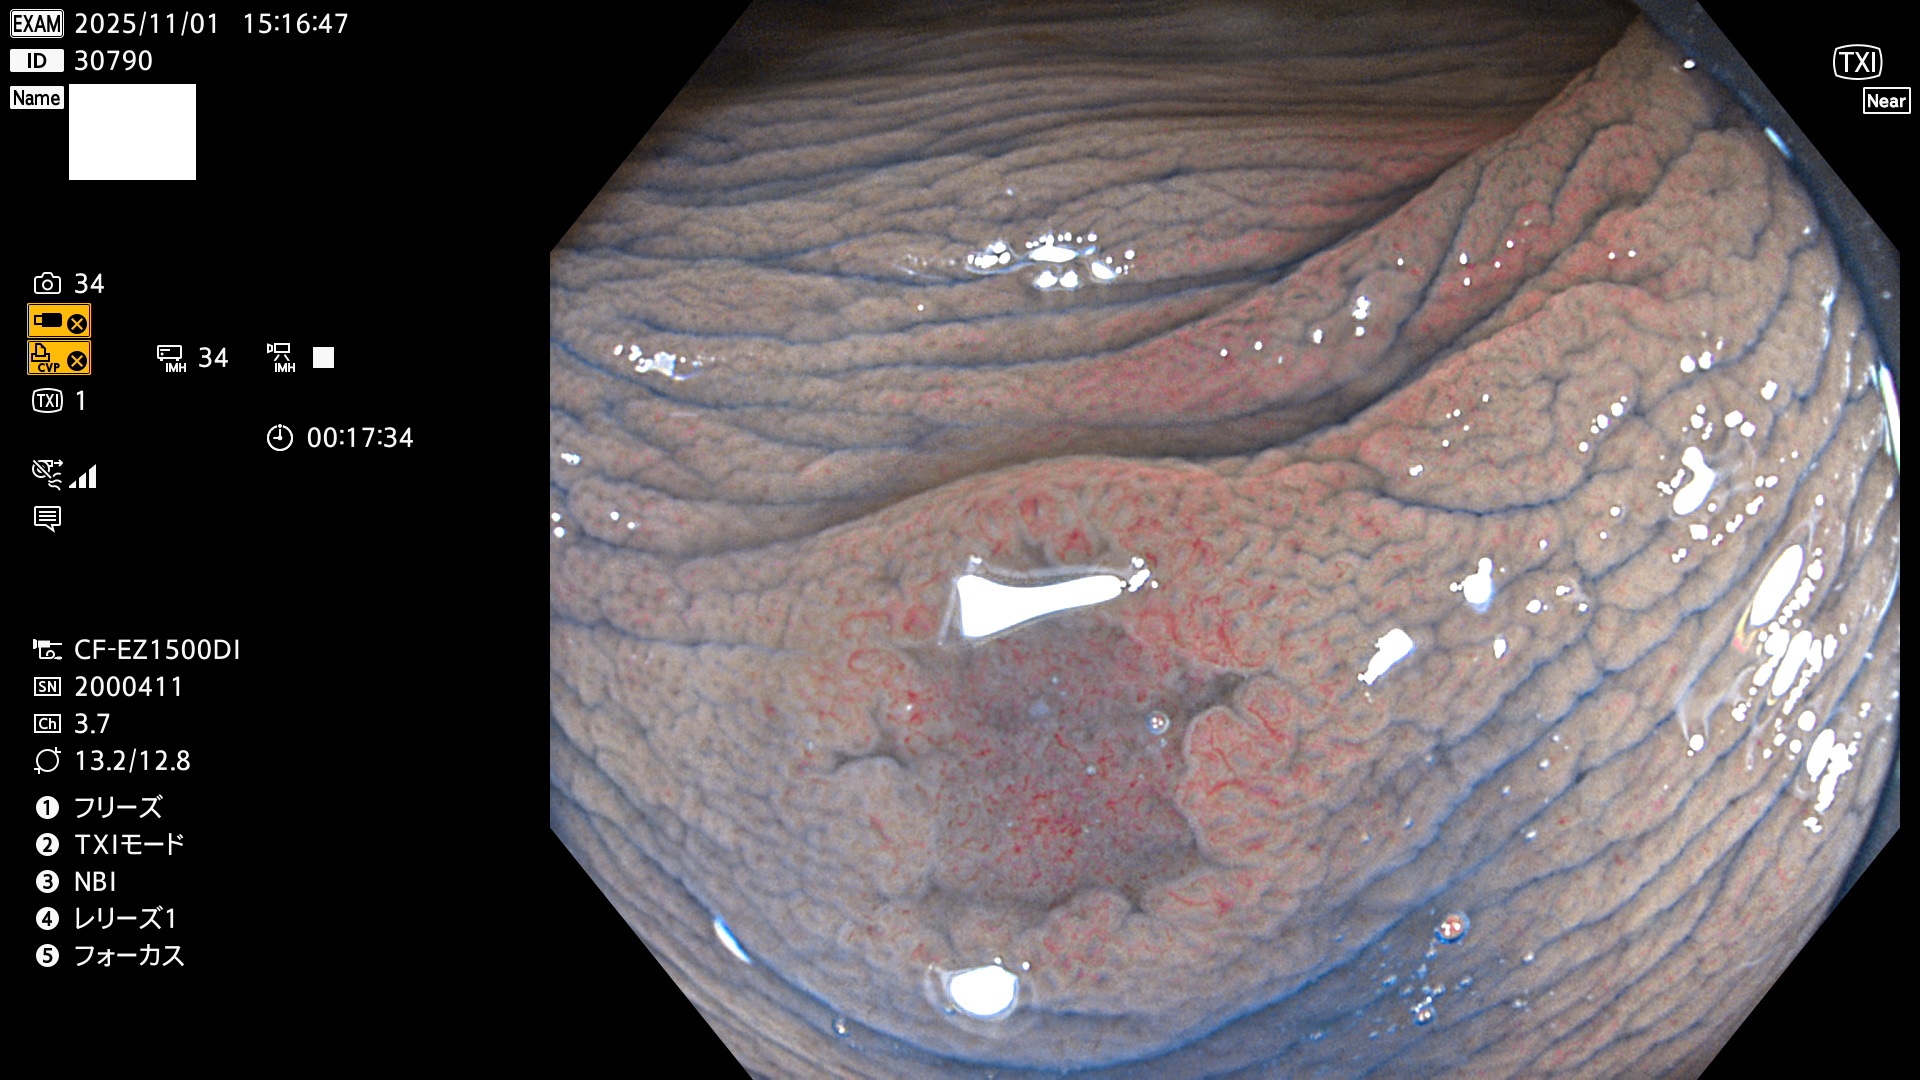

完全に平坦な物をUb、陥凹している物をUcと呼びます。Ubは認識が困難で、Ucはびらん(炎症)と紛らわしいために見落とされやすく、「内視鏡後・大腸癌」の原因になります。

毎週の検査(木・金・土・日)に発見されたUbとUc型・腺腫を、その週の日曜の夜にUPし1週間、提示します。

2025年10月30日〜11月2日の4日間(40件)9個 (Uc_ADR=9個/40人=23%)